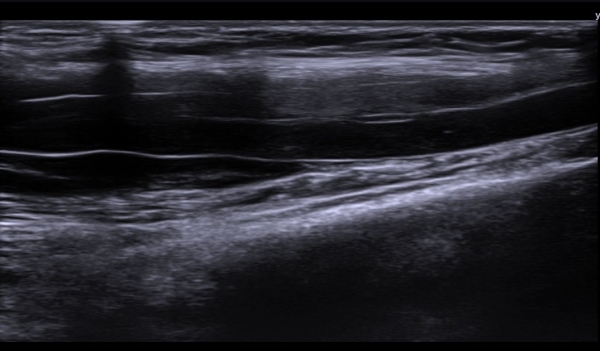

Á¤Á߽Űæ Ⱦ´Ü¸é°Ë»ç¿¡¼­µµ Á¤Á߽ŰæÀÌ Àú¿¡ÄÚ ºÎÁ¾ÀÌ ±æ°Ô  °üÂûµÇ°í ½ÇÁú³» ƯÁ¤ ¼¶À¯¼ÒÀÇ

Àú¿¡ÄÚ ºÎÁ¾ÀÌ ¶Ñ·ÇÇÏ´Ù(»çÁø 5, 6).